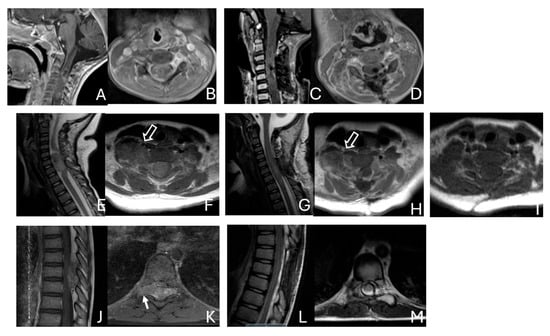

Objectives: Atypical teratoid/rhabdoid tumors (ATRTs) are rare, malignant central nervous system (CNS) neoplasms that predominantly affect infants and young children. While ATRT arises throughout the CNS, its extracranial counterpart, malignant rhabdoid tumor, occurs in other organs. A single-institutional cohort is reviewed to map

Objectives: Atypical teratoid/rhabdoid tumors (ATRTs) are rare, malignant central nervous system (CNS) neoplasms that predominantly affect infants and young children. While ATRT arises throughout the CNS, its extracranial counterpart, malignant rhabdoid tumor, occurs in other organs. A single-institutional cohort is reviewed to map anatomic distribution of pediatric ATRTs and to integrate a literature review to contextualize ATRT histogenesis from anatomical and embryological perspectives. Methods: A retrospective review was conducted on a cohort of 50 pediatric patients with ATRT treated over 20 years. Demographic, surgical, and neuroimaging data were correlated to define tumor location, extent, and compartmental involvement. A focused literature review synthesized molecular subclassifications and proposed cells of origin/cytogenesis. Results: Of the 50 ATRTs, 18 (36%) were infratentorial, 15 (30%) supratentorial, 11 (22%) in the pineal region, and 6 (12%) in the spinal compartment. Among infratentorial tumors, 10 were centered in the fourth ventricle, with or without extension into the cerebellopontine angle (CPA) cistern; the remainder arose in the CPA. Among ATRTs of the cerebral hemispheres, 3 showed bi-hemispheric involvement crossing the falx cerebri. ATRTs of the pineal region predominantly originated from the superior medullary velum. These topographic data were corelated with embryological and molecular information available in the literature. Conclusions: ATRTs arise across diverse neuroanatomical compartments—including intraparenchymal, intraventricular, extra-axial, and extradural sites—underscoring biological heterogeneity. Inactivation of SMARCB1 is the defining molecular event and principal oncogenic driver, although the upstream mechanisms precipitating these alterations remain incompletely resolved. Molecular subgroups—ATRT-TYR, ATRT-SHH, and ATRT-MYC—display distinct age distributions and anatomic predilections, implicating developmental context in tumor initiation. The characteristic cellular admixture of rhabdoid cells with mesenchymal and/or epithelial differentiation, together with intra- and extra-axial and occasional extradural presentations, supports a model in which at least a subset of ATRTs may originate from neural crest-derived lineages, despite little or no neural crest contribution to brain parenchyma development. Neural plate border progenitors with bipotent features represent a plausible intraparenchymal cell of origin. Definitive resolution of these origins and the mechanisms of SMARCB1 disruption will require integrated approaches. Further investigations are warranted to clarify these mechanisms.